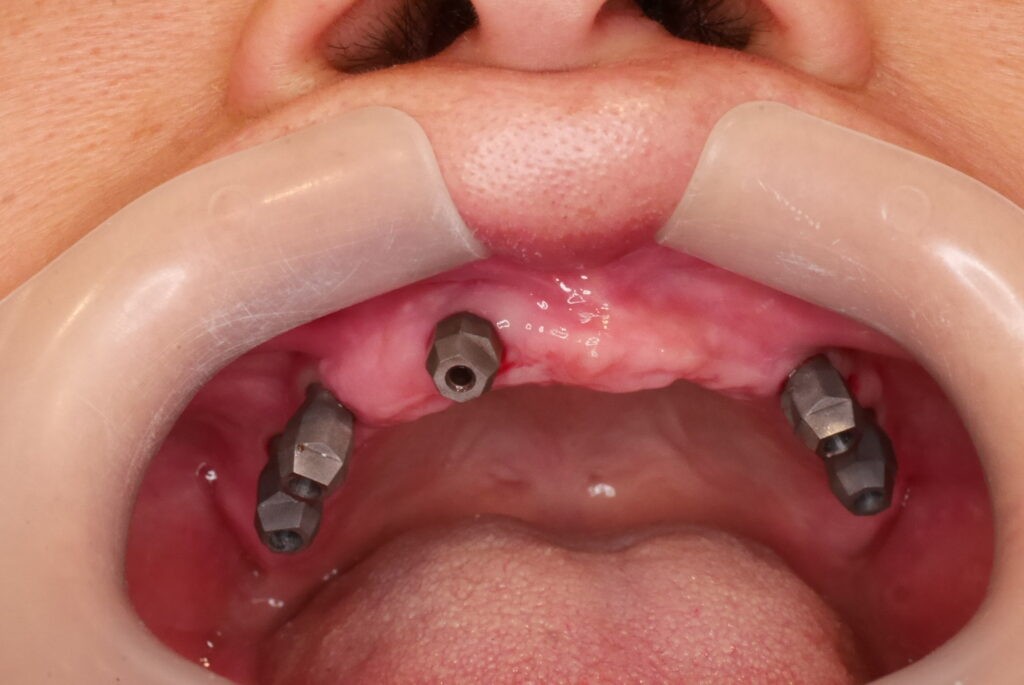

數位取模,置入植體掃描桿

數位取模 德國口掃機 口內精準掃描

數位取模 電腦設計 電腦製作